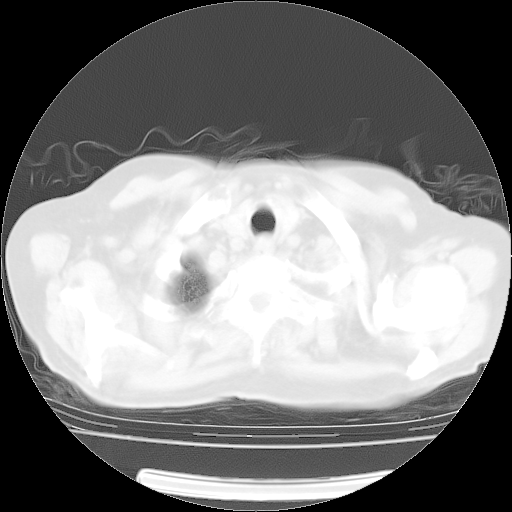

4月14日肺部CT

23.JPG

24.JPG

25.JPG

26.JPG

肺部CT平扫未见异常。